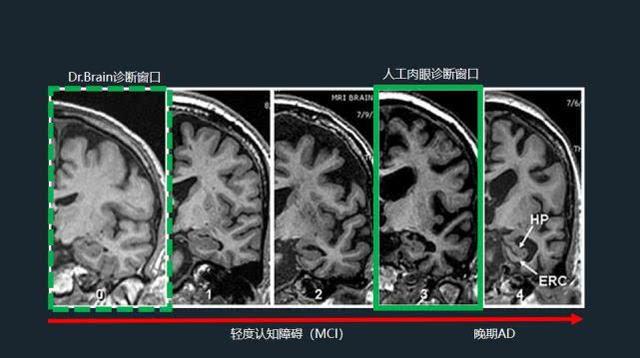

脑积水与脑萎缩的ct和mri诊断ppt课件

核磁报告"脑萎缩"就要痴呆了吗?听听"脑医生"如何解读

【读书笔记】两种常见脑萎缩ct表现

脑萎缩与正常人脑ct图

脑萎缩图片对比